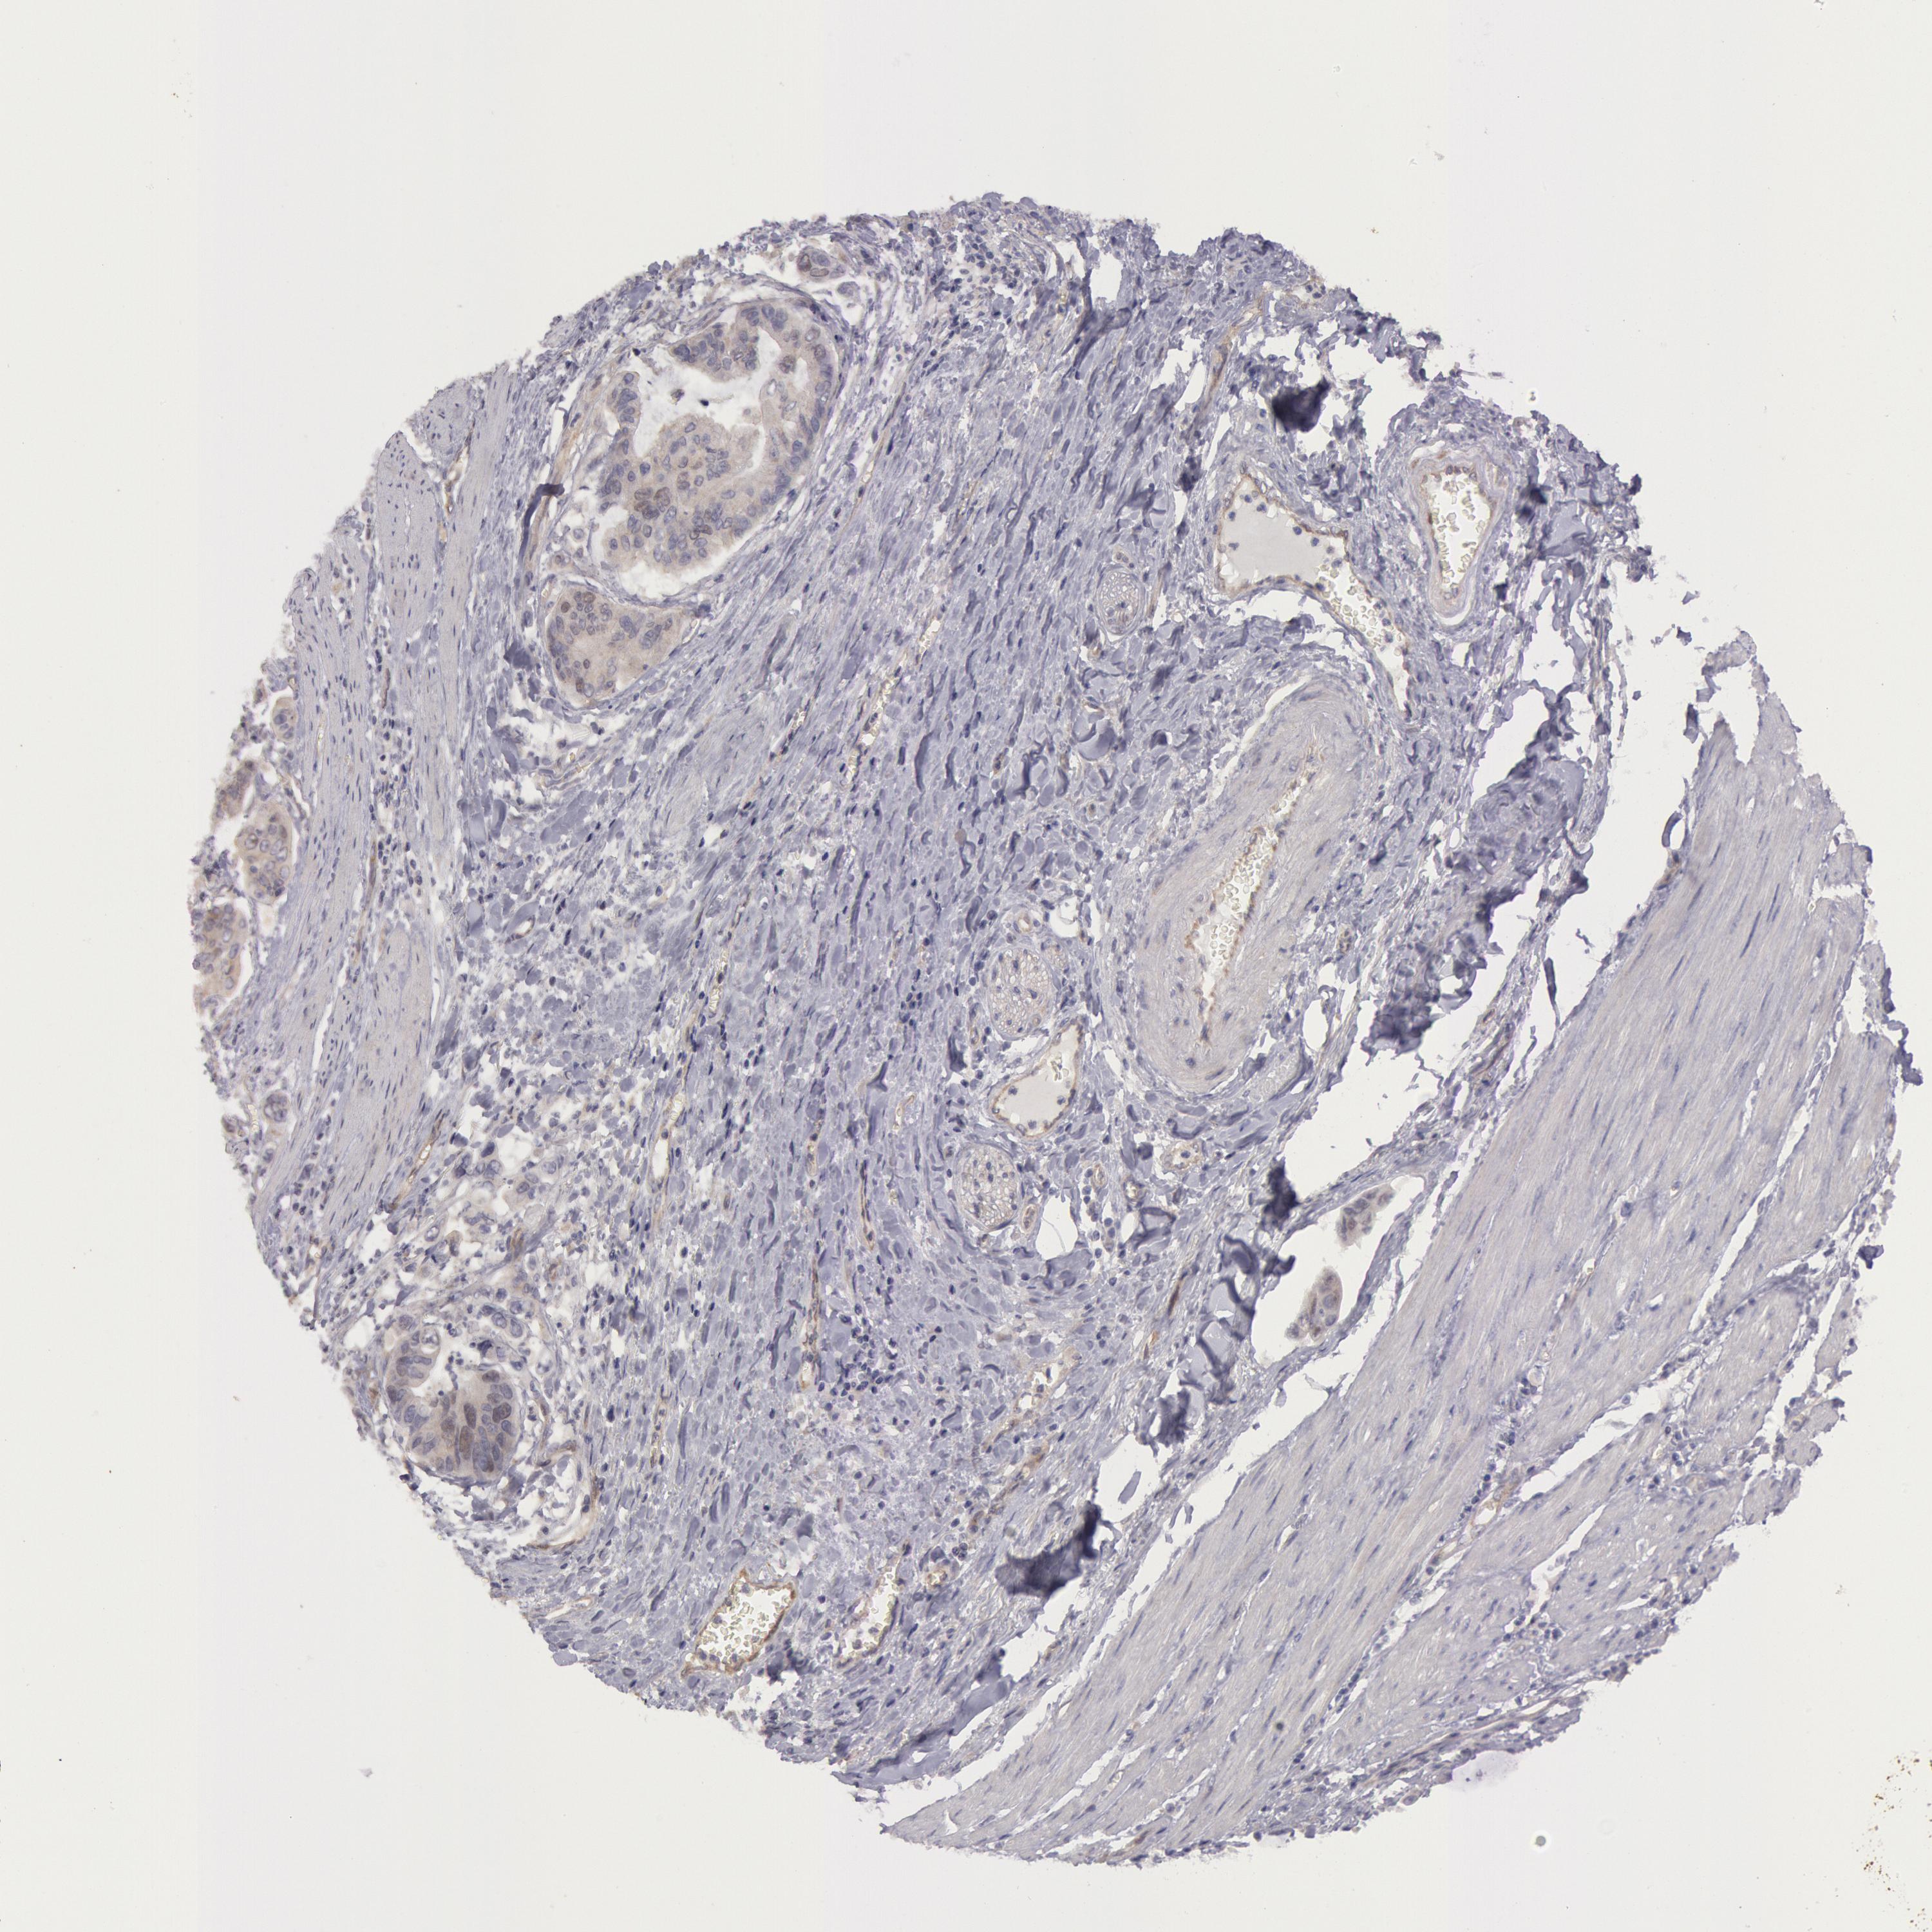

STOMACH CANCER - Protein expressioni

A mouse-over function shows sample information and annotation data. Click on an image to view it in a full screen mode. Samples can be filtered based on level of antibody staining by selecting one or several of the following categories: high, medium, low and not detected. The assay and annotation is described here.

Note that samples used for immunohistochemistry by the Human Protein Atlas do not correspond to samples in the TCGA dataset.

Antibody stainingi

Antibody staining in the annotated cell types in the current human tissue is reported as not detected, low, medium, or high, based on conventional immunohistochemistry profiling in selected tissues. This score is based on the combination of the staining intensity and fraction of stained cells.

Each image is clickable and will lead to virtual microscopy that enables deeper exploration of all samples and also displays staining intensity scores, fraction scores and subcellular localization as well as patient and tissue information for each sample.

Antibody HPA001196

Staining

High

Medium

Low

Not detected

Intensity

Strong

Moderate

Weak

Negative

Quantity

>75%

75%-25%

<25%

None

Location

Nuclear

Cytoplasmic/membranous

Cytoplasmic/membranous,nuclear

Adenocarcinoma, NOS